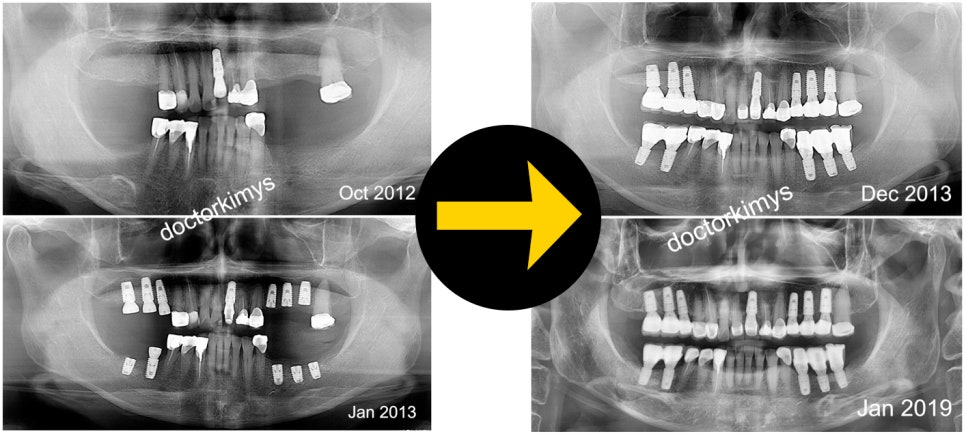

얼마전에 한 여성분께서 강남레옹치과에 방문하셨어요.

2012년에 처음 오셔서 어금니 전체를 수술하신 분인데요.

오랜만에 체크를 받으러 온 것이죠.

풀케이스다 보니까 끝나기까진 몇 개월이 걸렸어요.

그리고 6년이 지난 지금!

정말 건강하고 튼튼하게 사용중이시라 하네요?

저희 임플란트 노하우는 짧은 픽스쳐를 식립하는 것이에요.

쉬우면서 간단하고, 안전할 뿐만 아니라 효율적이기도 한 스타일이죠.

해당 여성분 사위가 고등학교 후배 분이셔서 정말 신중하고 정성스럽게 수술을 해드렸던 기억이 납니다.

이 사례를 해외 강의에서 보여주면 현지 의사들은 감탄을 쏟아내주시는데

그만큼 원장님의 임상경력과 실력은 의심할 여지가 없는 것 같아요.